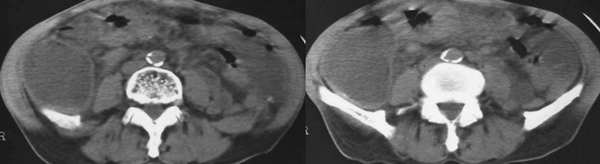

以下是引用wawaquan在2006-1-19 23:55:00的发言:[br]胆系结石,右半结肠梗阻:考虑横结肠占位(横结肠壁厚呈肿块状)。